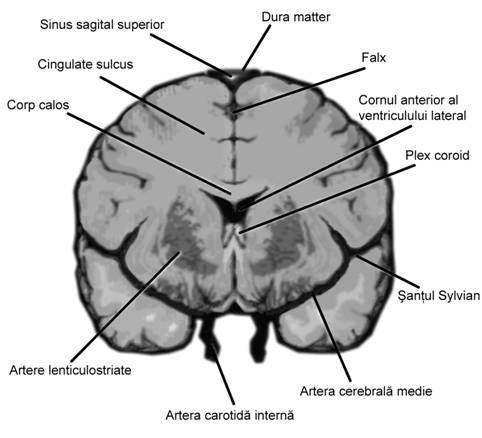

Linia de mijloc hiperecogena frontoocipitala este formata anterior si posterior de falx cerebri si fisura interemisferica, central de septum pellucidum. La sfarsitul primului trimestru de sarcina, linia de mijloc hiperecogena este flancata la distanta de o pereche de ventriculi laterali, ce inconjoara plexurile choroide ecogene. Din saptamana a 15-a cresterea cortexului devine vizibila, la marginea ventriculilor laterali, ca o margine hipoecogena. Partea posterioara a ventriculilor laterali ramane ocupata de plexurile choroide, in timp ce coarnele anterioare contin doar fluid. Dupa saptamana 19-a ventriculii laterali au caractere constante pe tot parcursul sarcinii.[1,3,8,13,14]

Fig. nr.163. Schita anatomica a creierului in sectiune coronala (frontala ). (adaptat dupa Pooh in [7])